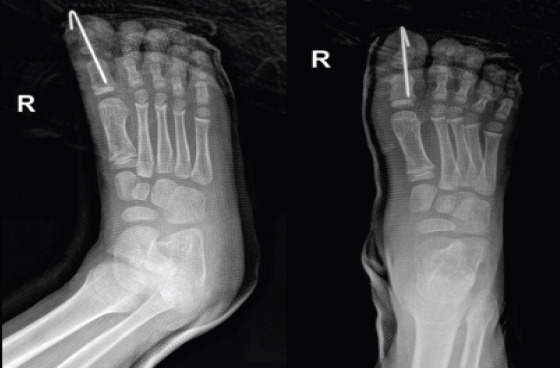

Case report: We report a case of open HIP joint dislocation in a 7-year-old boy surgically managed with irrigation and debridement and K-wire fixation. The HIP joint was found to be stable at 4 weeks after K-wire removal and the patient had full, painless HIP joint range of motion at 24 weeks.